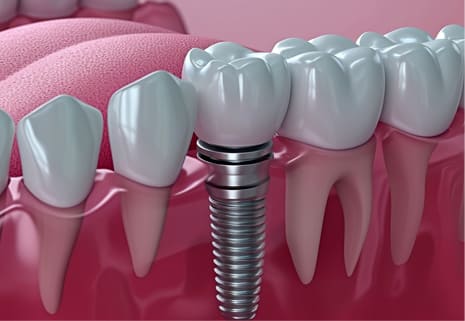

インプラント治療は、歯を失ってしまった場合の治療方法のひとつで、顎の骨に人工的な歯根(インプラント体)を埋め込み、その上から人工歯を被せていく治療法です。万が一、歯を失ってしまった場合でもインプラント治療によって、天然歯と同じような感覚で、快適に日常生活を送ることができます。入れ歯やブリッジなどを検討されている方も、インプラント治療を一度ご検討いただければと思います。

歯を失った場合の治療としてブリッジという方法がありますが、健康な歯を削る必要があります。インプラントなら周りの歯へ負担をかけずに治療が可能です。

インプラント体を顎の骨に埋め込んで、その上からジルコニアなどセラミック製の人工歯を被せるため、他の治療法と比較しても非常にきれいな見た目に仕上がります。

インプラントを埋入すると、天然歯のようにしっかりと噛むことができるためお口の筋肉もしっかりと使うことができ、顎が痩せるのを防ぐことにつながります。

インプラントとあごの骨が結合する期間(3~6か月)を置いて、人工歯を作製します。インプラントに取り付けた蓋を外してアバットメント(人工歯の土台)を取り付けて、人工歯を被せて治療は完了です。